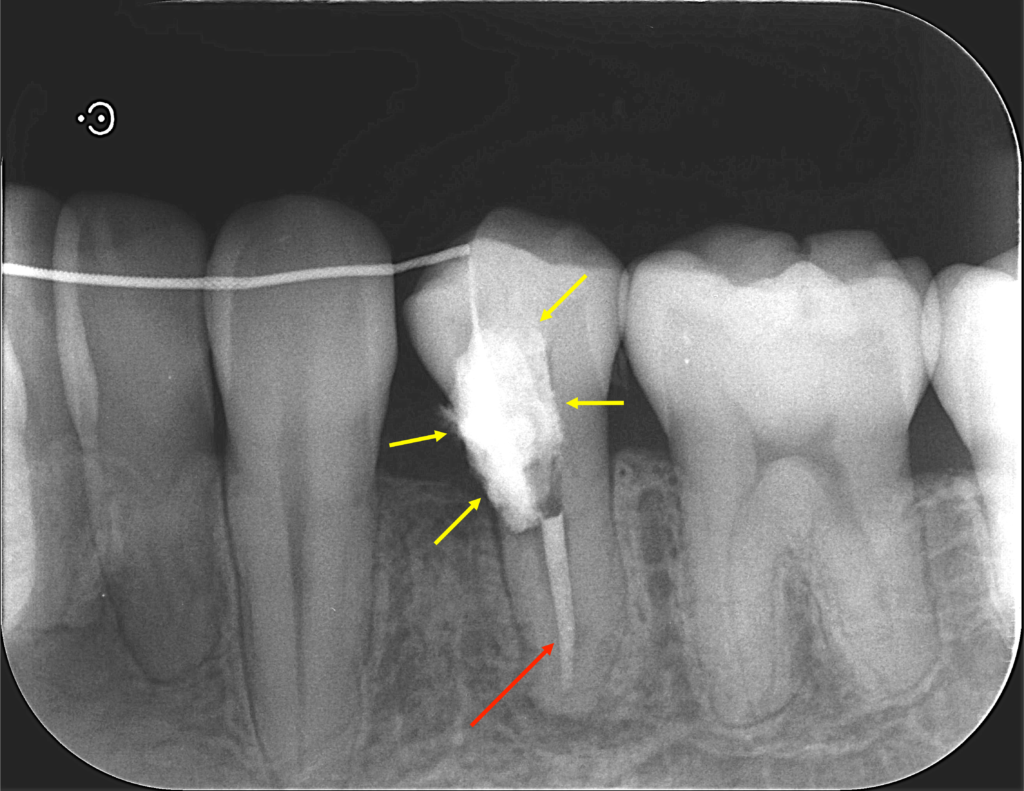

言葉で書くのは簡単ですが、これには非常に時間がかかりとても困難な治療でした。そこにMTAセメントを用い、根の先端の方(赤矢印)と吸収部(黄色矢印)を同時に埋めました。

黄色矢印の左の方を見ていただくとわかると思いますが、外にはみ出しているのがわかるかと思います。

これはMTAセメントを押し込んで、わざとはみ出しています。

この後歯茎を開いて、はみ出したMTAセメントと除去しきれていない外部吸収部を除去して、グラスアイオノマーというセメントにより同部を埋めました(赤矢印)。

これも言葉にして書くと簡単なのですが、これをピッタリ埋めるのが非常に難しかったです。